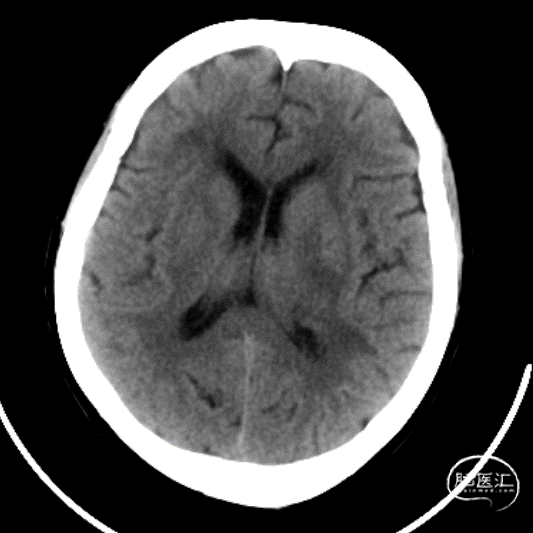

既往史:患者于入院前3小时工作时无明显原因及诱因出现右侧肢体无力,伴短暂意识丧失,随后患者呈嗜睡状,无恶心、呕吐,经短暂休息后,未见好转,经120送入我院急诊,急诊行头颅CT示:左侧丘脑出血破入脑室,出血量约为20ml。

辅助检查:头颅CT(我院):右侧丘脑出血破入脑室,出血量约20ml。

术前